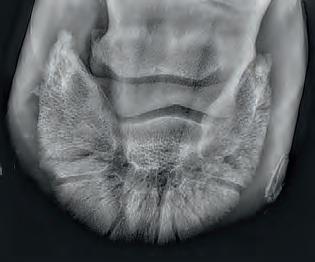

Radiographic proof in clinical results

BONE Gold nutritional bone joint and collagen supplement was formulated to provide some of the essential amino acid requirements of collagen type I, II and III (found in bone and connective tissue) in addition to supporting the nitric oxide pathway which has been found to assist in the formation of bone callus postinjury.

Veterinary surgeons have recommended that Bone Gold may assist with sore shins, tendon injuries, ligament injuries, osteoarthritis and post-surgery in horses and polyarthritis, geriatric osteoarthritis, and post-surgery in dogs.

Here is a veterinary radiographic report on a horse with a fracture evident on the medial toe and after treatment and feeding Bone Gold during this period. More information on these products can be found at www.vetgold.com.au

VETERINARY RADIOGRAPHIC REPORT

HORSE: "XXXXXXXX"

DATES OF EXAMINATION: 26TH AUG, 21ST OCT 21 & 17TH NOV '21

PLACE: XXXXXXXXXX FARM

XXXXXXX's left and right front feet were radiographed on 26th Aug, 21st Oct (8 weeks) and again on the 17th Nov '21(12 weeks).

RADIOGRAPHS:

26.08.21: Right Front: Large P3 solar margin fracture evident on medial toe 32.6mm x 4.1mm with approximately 1.4mm separation from parent bone as below left image.

21.10.21: Right Front: Fine residual 4.2mm fracture still evident, approximately 90% resolution

17.11.21: Right Front: Fracture fully resolved

RECOMMENDATIONS:

Radiographic results as of the 17th Nov '21 show total resolution of the original fracture.

XXXXXXX was reshod today utilising off an alloy shoe with a toe clip - inner circumference seated out to avoid any sole pressure.

The horse can return to training. Please do not hesitate to contact me if you have any further queries

COMMENTS:

Solar margin Type IV fractures of this magnitude have well-documented internationally published healing rates of 7 - 12 months. Full resolution of these fractures is rare as most often the fracture fragments are resorbed.

Full resolution in a 3 month period was not anticipated.

The horse was on Bone Gold 3 x scoops fed once per day for this period.

"Go to our webpage or scan the QR Code to see more Bone Gold Radiographic results"